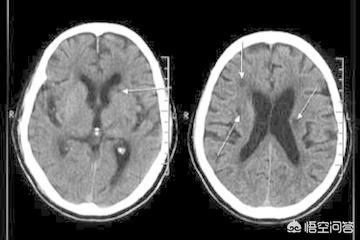

脳梗塞発症後24〜48時間後に脳のCT検査を行うと、対応する部位に境界のはっきりしない低密度の病巣が認められ、何らかの占拠作用がある可能性がある。脳磁気共鳴(MRI)検査では、病変部のT1低信号と加重画像のT2高信号によって示される脳梗塞を早期に発見することができ、MRIはより小さな梗塞病変を検出することができる。

空洞性脳梗塞の病変は小さく、専門医でなければ容易に認識できない。